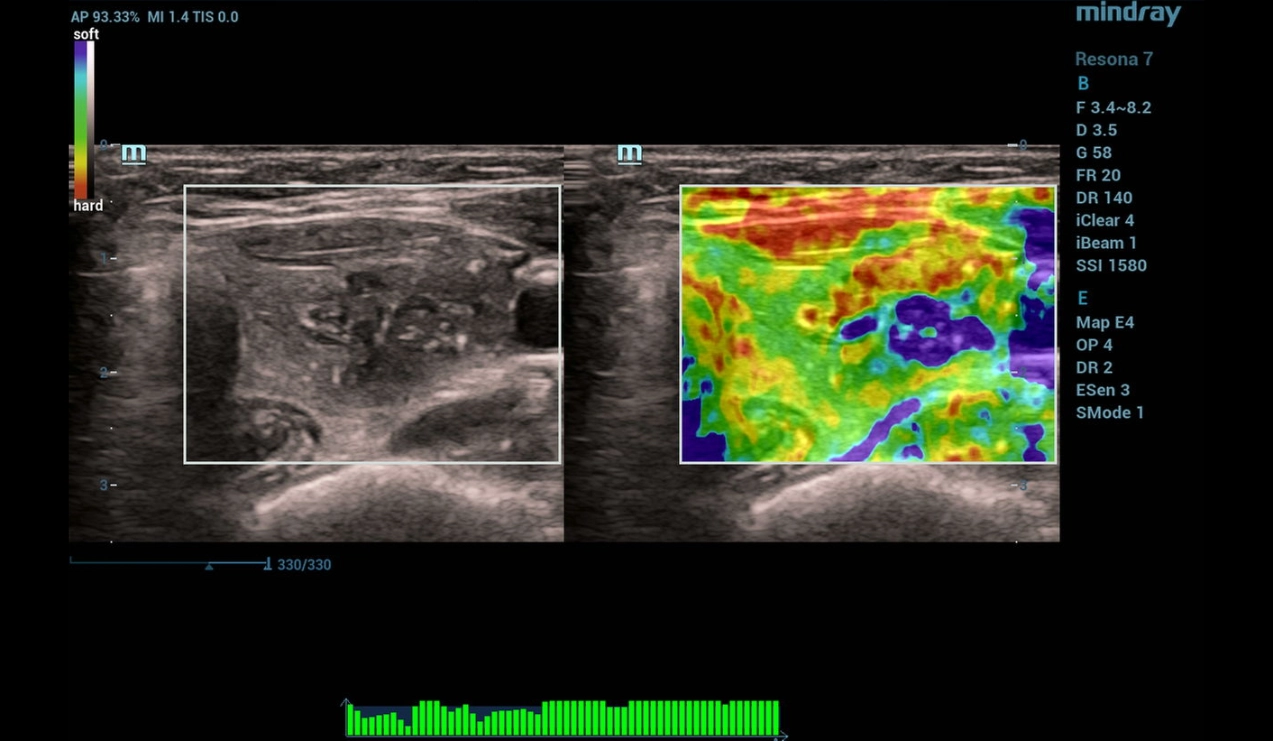

Strain elastography

Strain elastography identifies a tricolor structure (BGR sign - blue/green/red layers) of the focal mass, which is consistent with cystic contents (Figure 3).

Figure 3. Strain elastography image of the thyroid

On strain elastography, the focus had tricolor staining (BGR sign) consistent with a cystic mass.